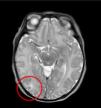

El electroencefalograma y la resonancia magnética cerebral evidenciaron respectivamente anomalías paroxísticas temporales bilaterales y una discreta hiperseñal en T2 en la sustancia blanca subcortical temporal posterior derecha (fig. 2).